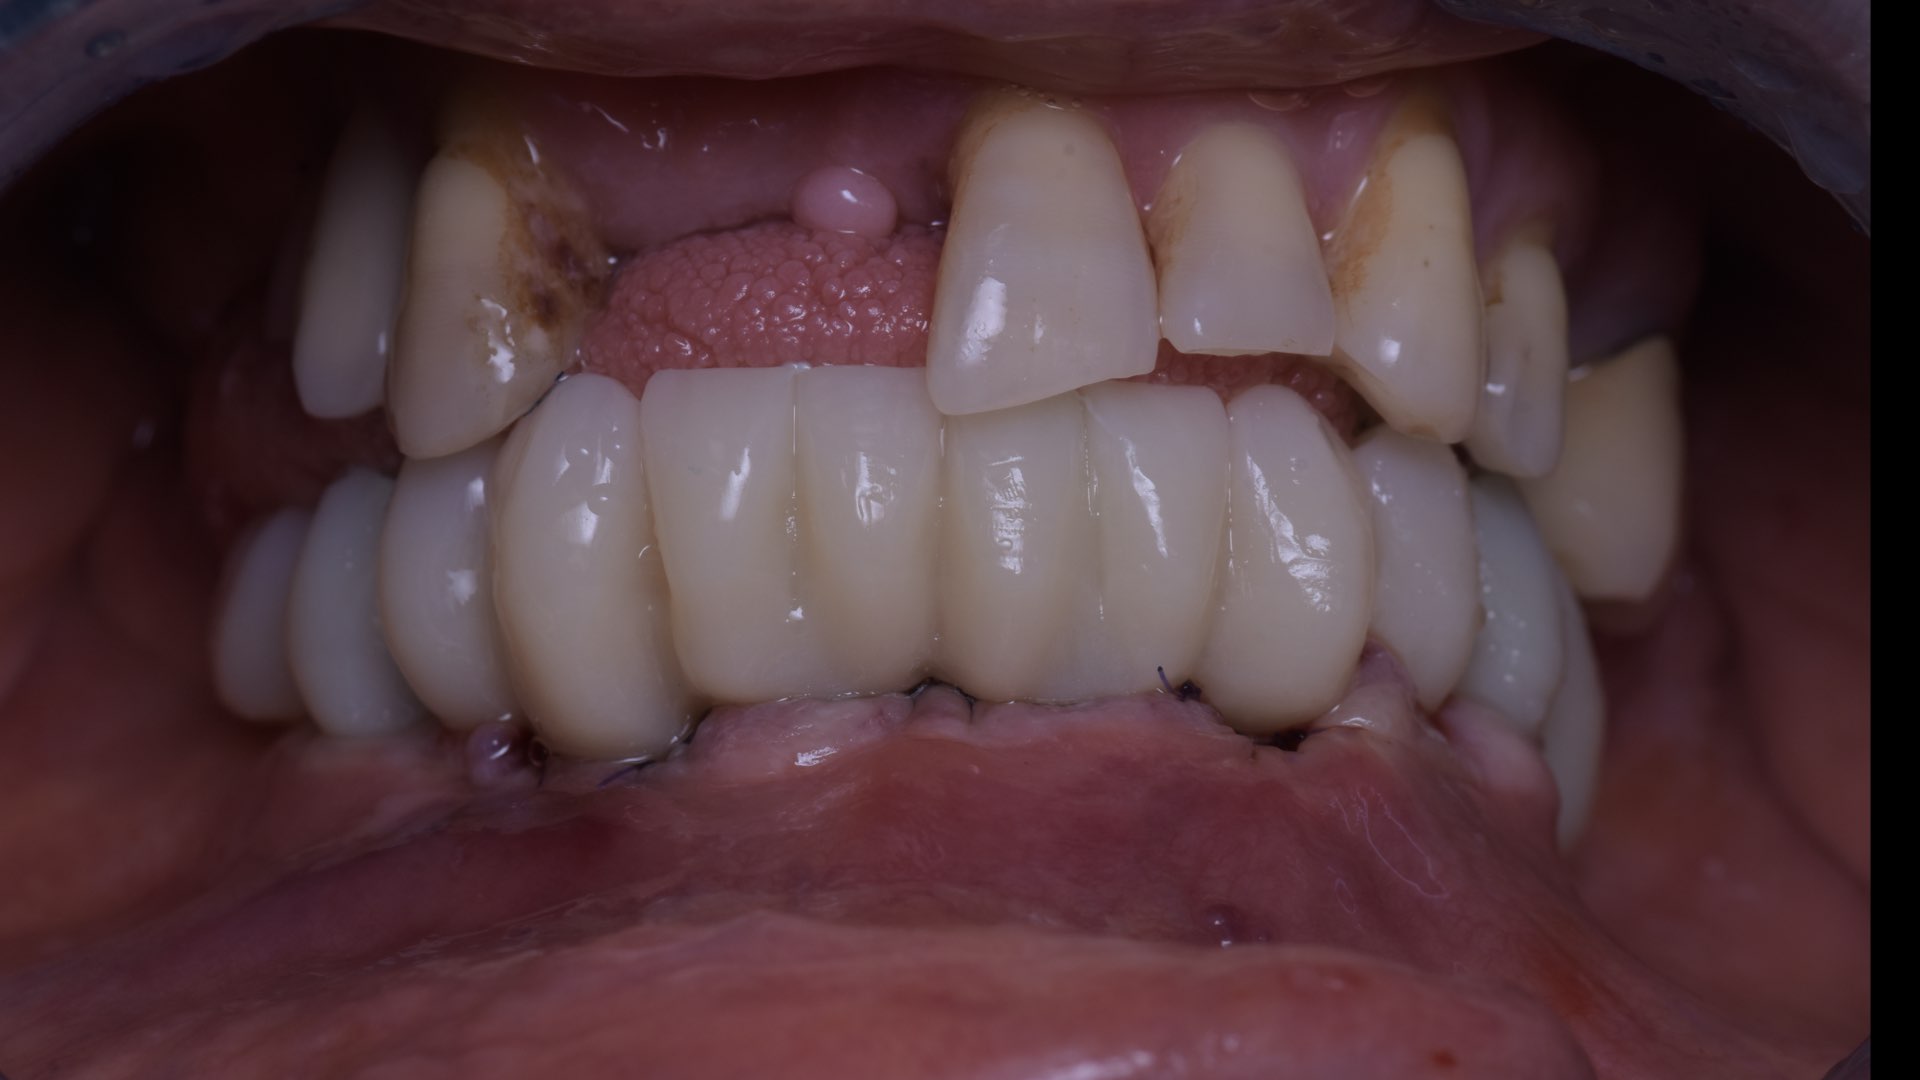

Les deux bridges provisoires sont vissés par l’intermédiaire de vario-bases à la mandibule et au maxillaire (Fig. 16). Nous réhabilitons le patient grâce à la réalisation d’un bridge full zircone à connexion directe sur multi-unit au maxillaire.

À la mandibule un bridge PMMA sur vario-base est vissé. Nous n’optons pas pour la réalisation de deux bridges full zircone, pour des questions de dureté de matériaux et de confort pour le patient. Nous combinons l’esthétique d’un bridge full zircone au maxillaire et la souplesse du PMMA à la mandibule (Fig. 17). La photo avant-après du patient, illustrant son état au premier jour et à la fin de son traitement, est présentée sur la figure 18.